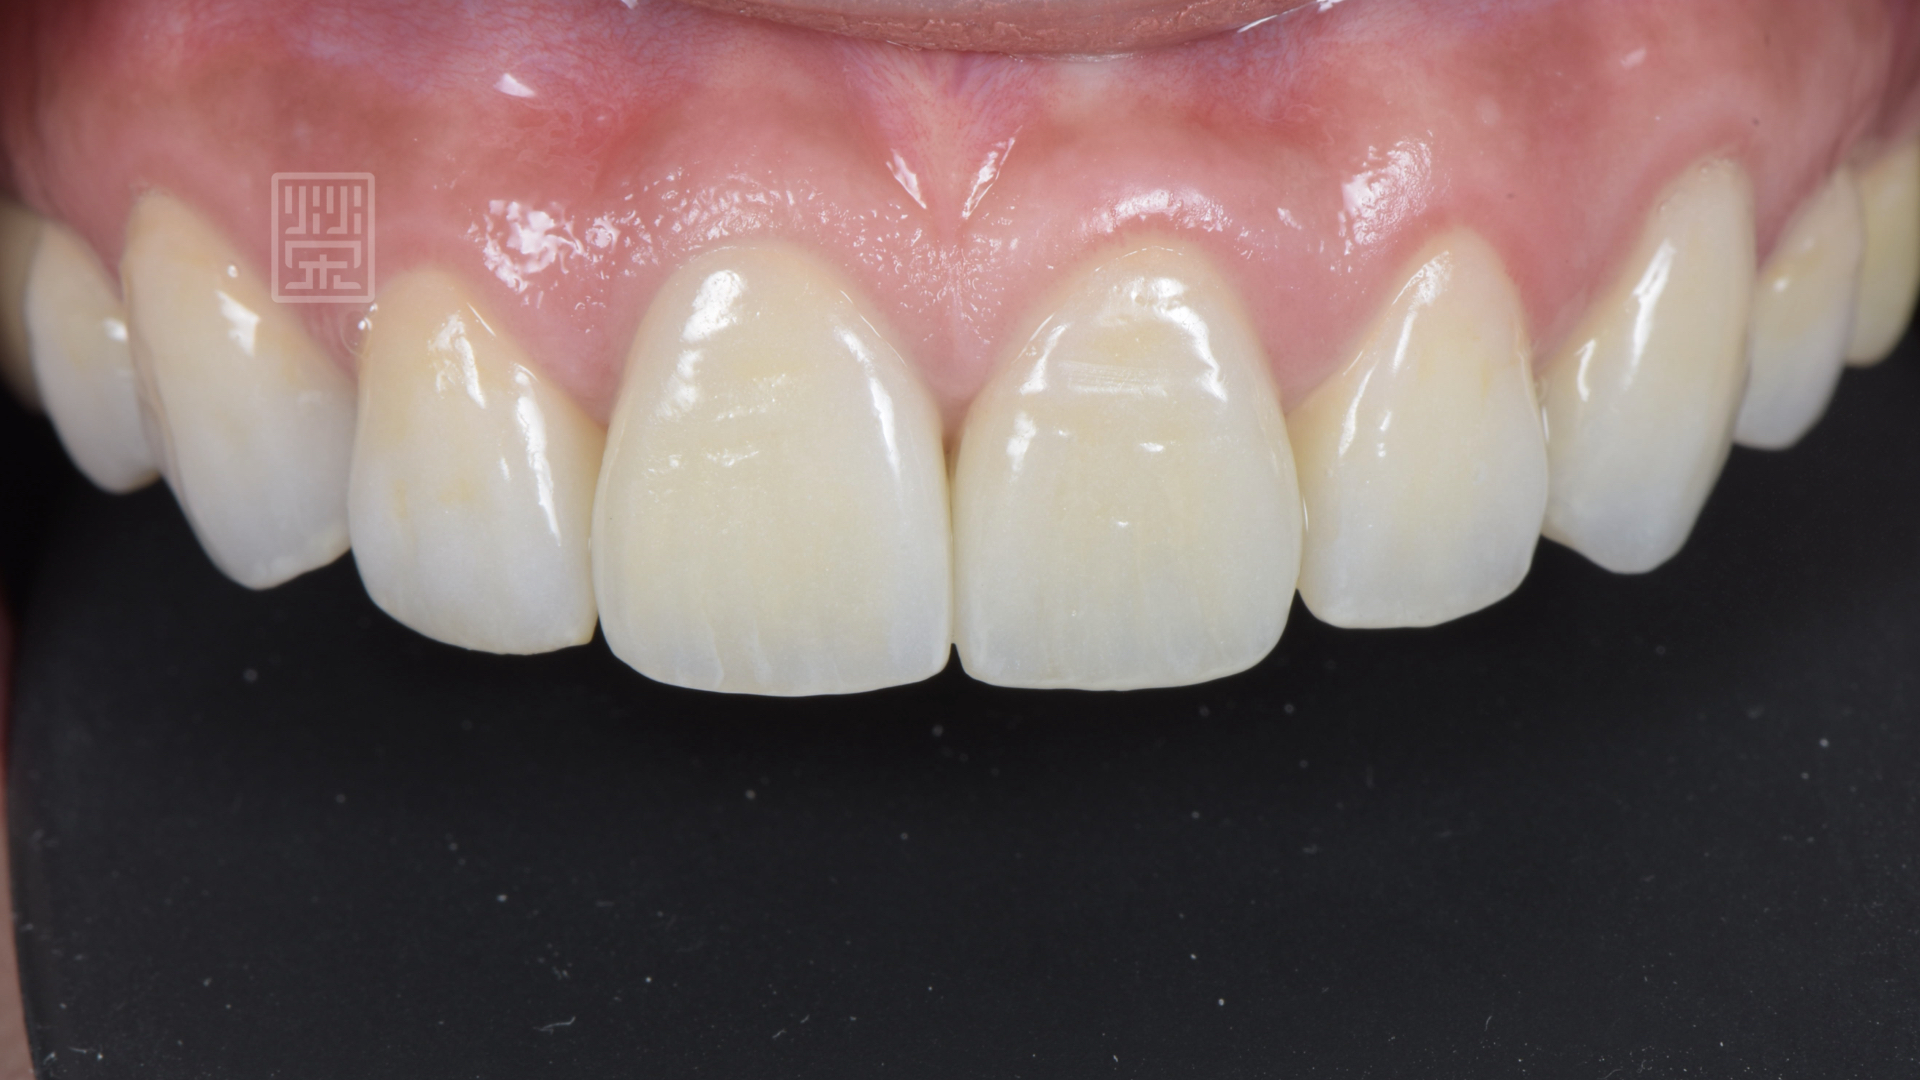

等到植體癒合穩定後,針對牙齒的長度為製作模擬溝通,顏色部分希望自然白亮即可,所以選擇自然齒色中最白亮的色階,讓整體笑容更加和諧。

植牙、全瓷冠、全瓷貼片完成

前後對比